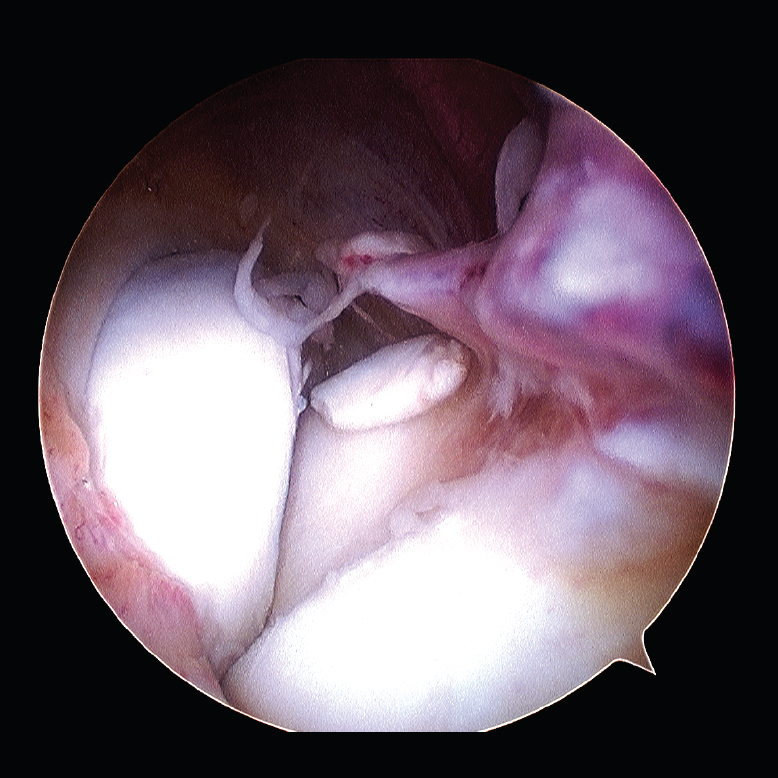

La resonancia magnética (RM) puede ser útil para valorar el cartílago articular, la fibrosis articular y periarticular, el estado ligamentoso y la presencia de cuerpos libres no calcificados (Figura 3).

Figura 3. Fibrosis articular, imagen de resonancia magnética.